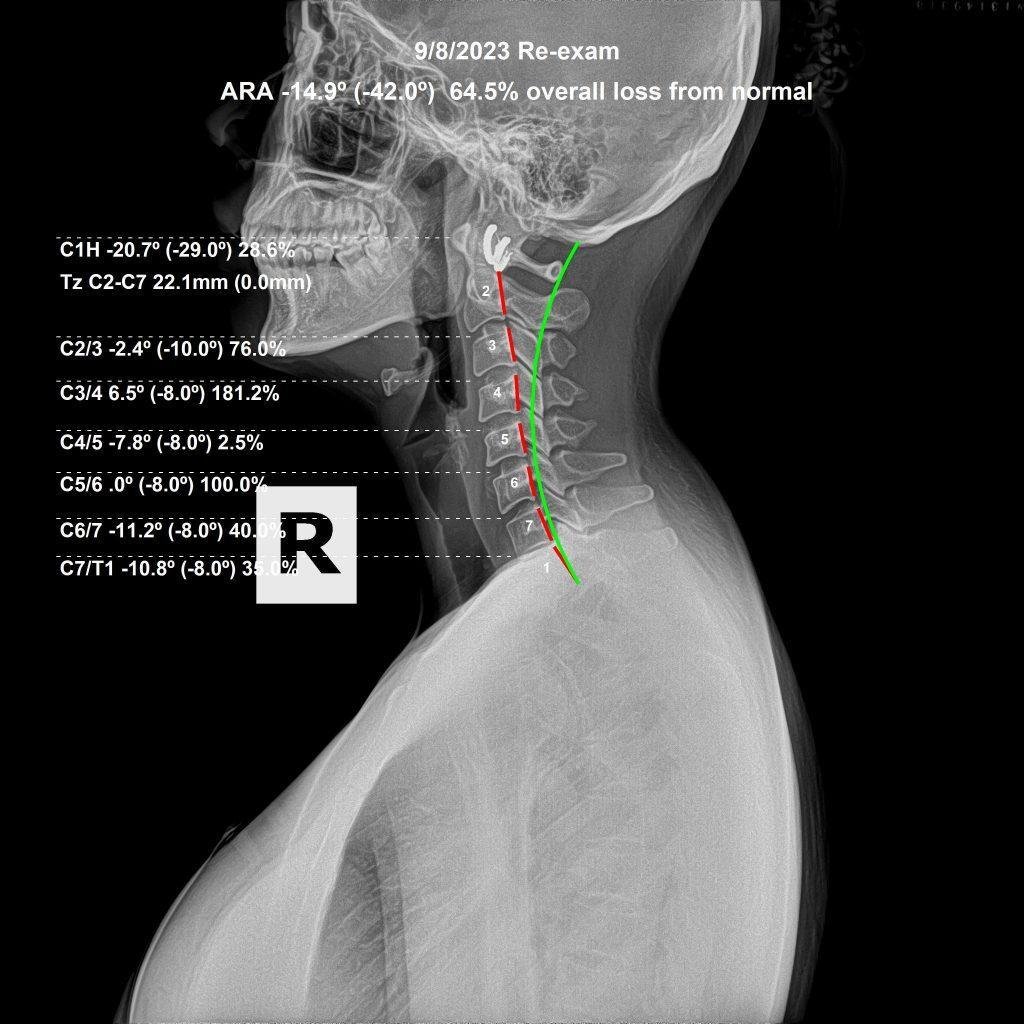

Before & After Structural Analysis

Subluxation correction is not a single event. It is a process of progressive structural change over time, documented through follow-up X-rays taken after a period of care. The before-and-after films below are representative of what correction actually produces — measurable, visible change in spinal position and cervical curve.

After cervical X-ray — subluxation corrected, cervical curve restored

After Correction

What you are looking at is a change in the structural position of the cervical vertebrae — the curve deepening, the head position normalizing, the disc spaces becoming more uniform. This is what subluxation correction produces when care is specific, consistent, and properly analyzed at each visit.

This is also why we require X-rays before beginning care. Without a baseline film, there is no way to measure whether the spine is actually changing — or whether the adjustments being given are producing the structural outcome they should.